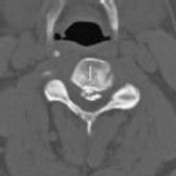

CLINICAL SITUATION

Figure 1 shows a CT from the cervical spine of an 85-year-old woman who fell from a standing height 1 week earlier. She is independent and ambulatory and resides in an assisted living facility. She reports persistent neck pain but denies arm pain or weakness. She is neurologically intact.

Fractures in this region of C2 have a high risk of

Discussion: C

Increased displacement and angulation of odontoid fractures have an increased risk of nonunion. Surgical stabilization has reduced the risks of mortality without increasing the risk of complications compared with nonsurgical treatment options. When treating odontoid fractures, halo vest

immobilization has been shown to increase the risk of dysphagia in the elderly.

Question 7 of 100

The preferred mode of treatment for this patient’s fracture is

4. posterior C1-2 arthrodesis. Discussion: D

Increased displacement and angulation of odontoid fractures have an increased risk of nonunion. Surgical stabilization has reduced the risks of mortality without increasing the risk of complications compared with nonsurgical treatment options. When treating odontoid fractures, halo vest immobilization has been shown to increase the risk of dysphagia in the elderly.

Question 8 of 100

What are the risks associated with halo vest treatment, compared with hard-collar treatment?

4. Dysphonia Discussion: B

Increased displacement and angulation of odontoid fractures have an increased risk of nonunion. Surgical stabilization has reduced the risks of mortality without increasing the risk of complications compared with nonsurgical treatment